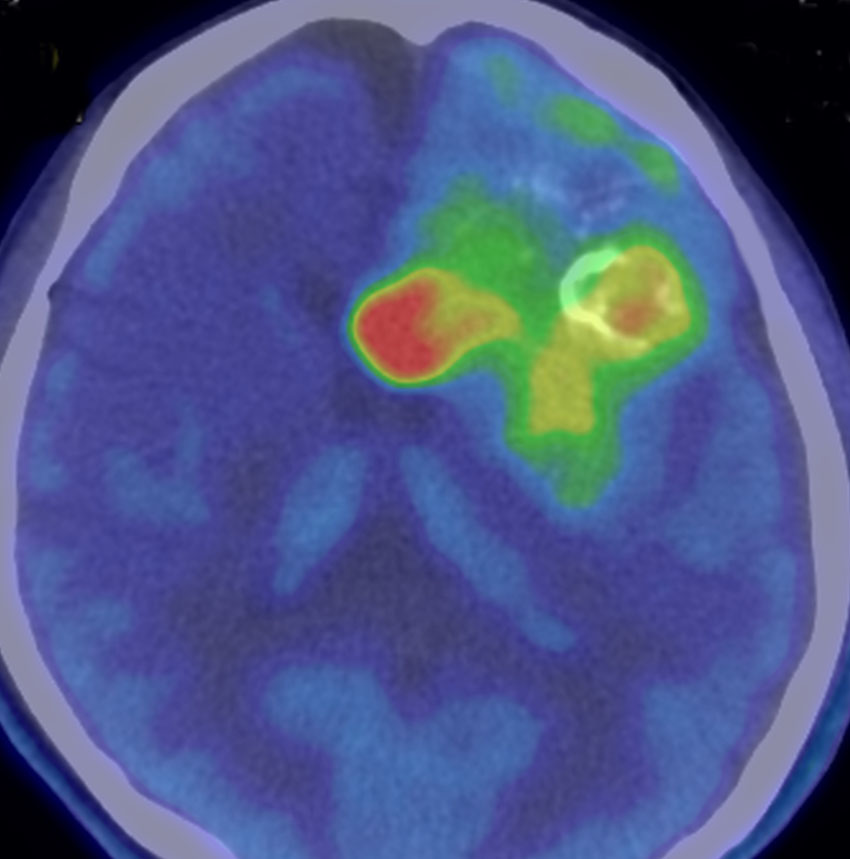

メチオニンペット Met-PET

11C-メチオニンという放射性物質を静脈から注射して,脳のPET(ポジトロン断層撮影)をします。メチオニンの取り込みが高いところが赤く描出されます。グリオーマと炎症性疾患や壊死などとの鑑別に迷った時に用いられることがあります。グリオーマでは,悪性度の高いもの,乏突起膠腫に取り込みが高く見られますが,病理診断を超える価値はありません。

これを見たからといってグリオーマの治療方法が変わるわけではありませんから,保険診療は認められていません。自己負担で6万円以上はかかるでしょう。